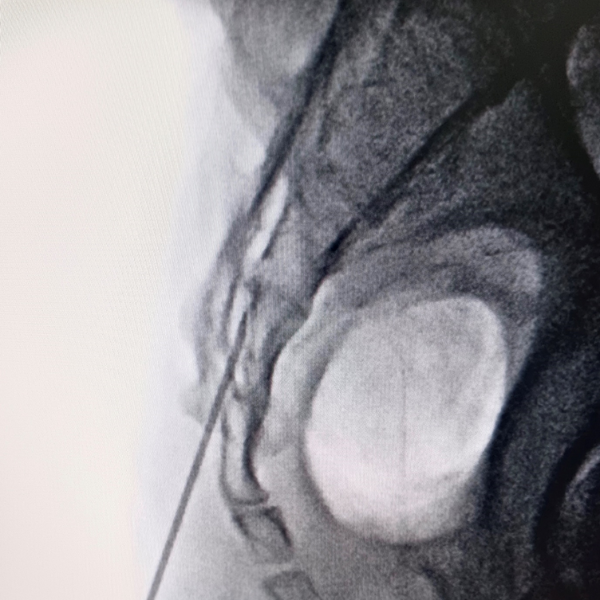

Cervical Myelopathy Expert Care by Dr. Nitish Agrawal – Best Spine Surgeon in Pune Cervical Myelopathy is a serious spinal condition in which the spinal cord in the neck (cervical spine) becomes compressed. This compression is most commonly caused by degenerative changes in the spine, such as cervical disc prolapse,…